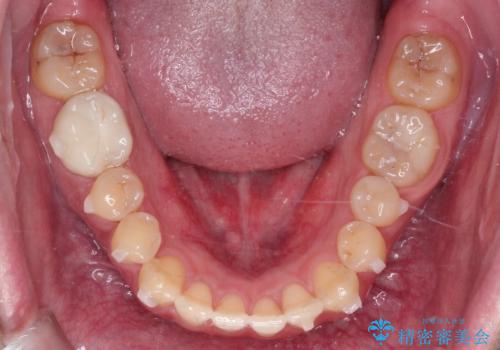

- 前歯の咬み合わせが気になるとのことで来院されました。

前歯が噛んでいない状態(開咬)のため、インビザライン矯正で改善することとしました。

前歯が嚙んでない場合(開咬)、顎間ゴムというゴムを使用してもらうことがあります。顎間ゴムは、前歯を噛み合わせるための力を与える補助的な役割があります。

マウスピース矯正は、患者様のご協力が重要です。マウスピースをきちんと装着し、歯科医院での定期検診が必要になります。